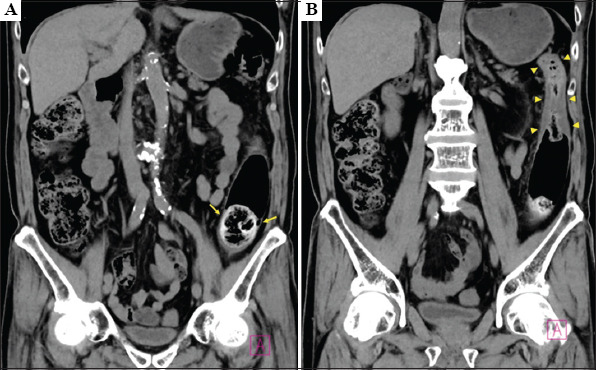

Background and aim: A 75-year-old man who had eaten half a head of chopped raw cabbage (approximately 600 g) daily was suffering from the left lower pain, abdominal fullness, and constipation. He was diagnosed with colonic ileus and obstructive colitis due to a fecal impaction in the sigmoid-descending junction. During colonoscopy, a tapered catheter was repeatedly inserted into the impacted feces to inject a bowel-cleansing agent. Finally, the feces were broken to be fragmented enough to path the endoscope through. After the procedure, his symptoms were immediately relieved.

Relevance for patients: Excessive dietary fiber intake can induce fecal ileus. Endoscopic treatment with intra-fecal injection of a bowel-cleansing agent is useful and worth attempting for disimpaction of feces.